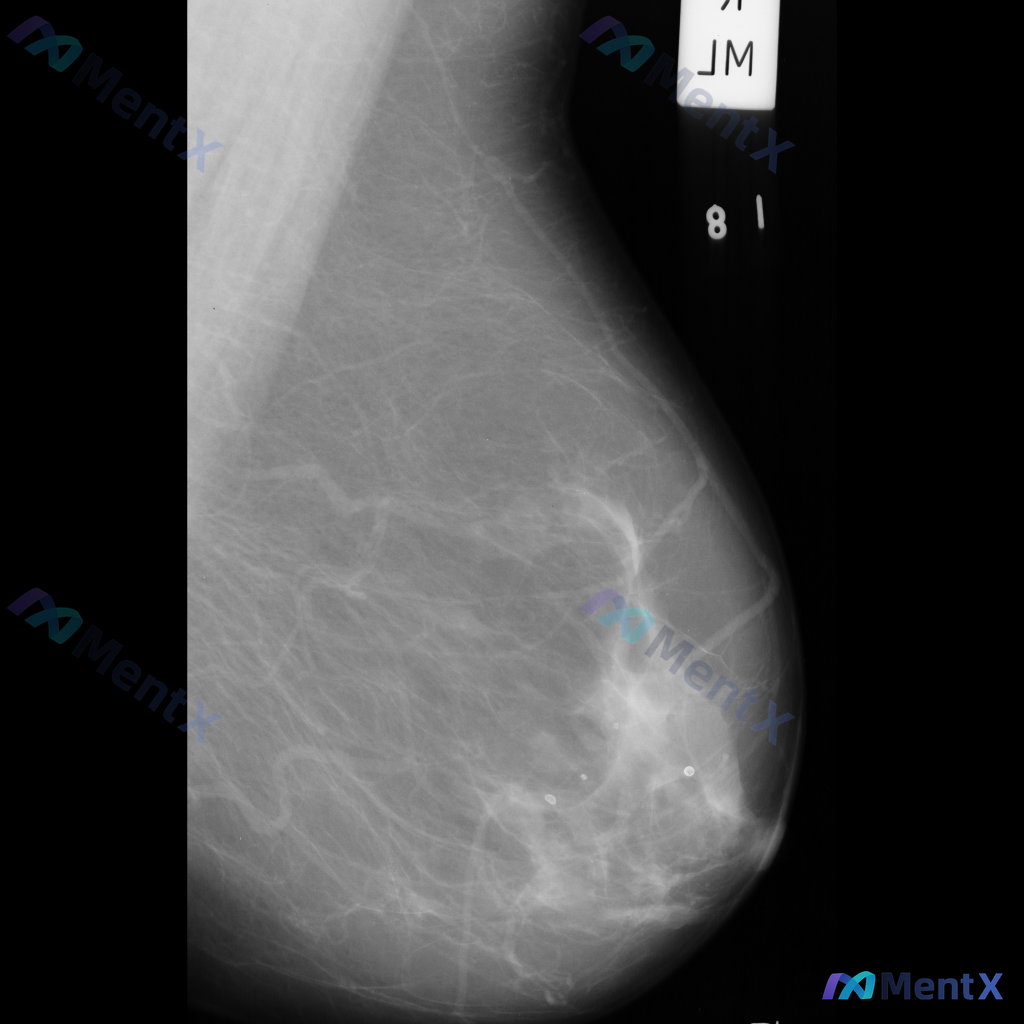

整理到一份乳腺钼靶影像资料,主要异常表现如下: - 部位:乳腺中部偏下方 - 影像征象:局灶性不规则腺体密度增高,伴结构扭曲 - 背景:致密型乳腺 目前仅单张影像资料,未提供其他体位、超声或临床病史。 想和大家讨论一下:单看这组异常表现,你会先往哪个方向考虑?后续如果要进一步明确,你觉得优先做什么检...

整理到一组乳腺钼靶影像的资料,分享给大家讨论: - 背景:不均匀致密型乳腺(BI-RADS C类) - 主要异常: 1. 乳腺下象限靠近乳头乳晕区,见两个大小不一的圆形/卵圆形高密度影,还有一个较小的类圆形高密度影,密度高于周围腺体,边缘相对清晰但略显模糊; 2. 上述高密度影周围的乳腺下象限,腺体...